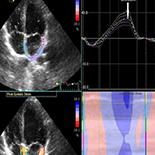

We enrolled 74 non-ST segment elevation myocardial infarction patients who were treated with percutaneous coronary intervention and 58 healthy control subjects. Non-ST segment elevation myocardial infarction patients had echocardiographic examination 48 h after the percutaneous coronary intervention procedure and venous blood samples were drawn simultaneously. In addition to conventional echocardiographic parameters, left atrial strain curves were obtained for each patient. Average peak left atrial strain values during left ventricular systole were measured.

BNP values were higher in non-ST segment elevation myocardial infarction patients compared to controls. Mean left atrium peak systolic global longitudinal strain in Group 2 (the control group) was higher than in the non-ST segment elevation myocardial infarction group. Left atrium peak systolic global longitudinal strain was significantly correlated with left ventricular ejection fraction. There was a significant inverse correlation between left atrium peak systolic global longitudinal strain and brain natriuretic peptide level, left atrium volume maximum, and left atrium volume minimum.

Our study shows that Left atrium peak systolic global longitudinal strain values decreased consistently with deteriorating systolic and diastolic function in non-ST segment elevation myocardial infarction patients treated with percutaneous coronary intervention. Left atrium peak systolic global longitudinal strain measurements may be helpful as a complimentary method to evaluate diastolic function in this patient population.